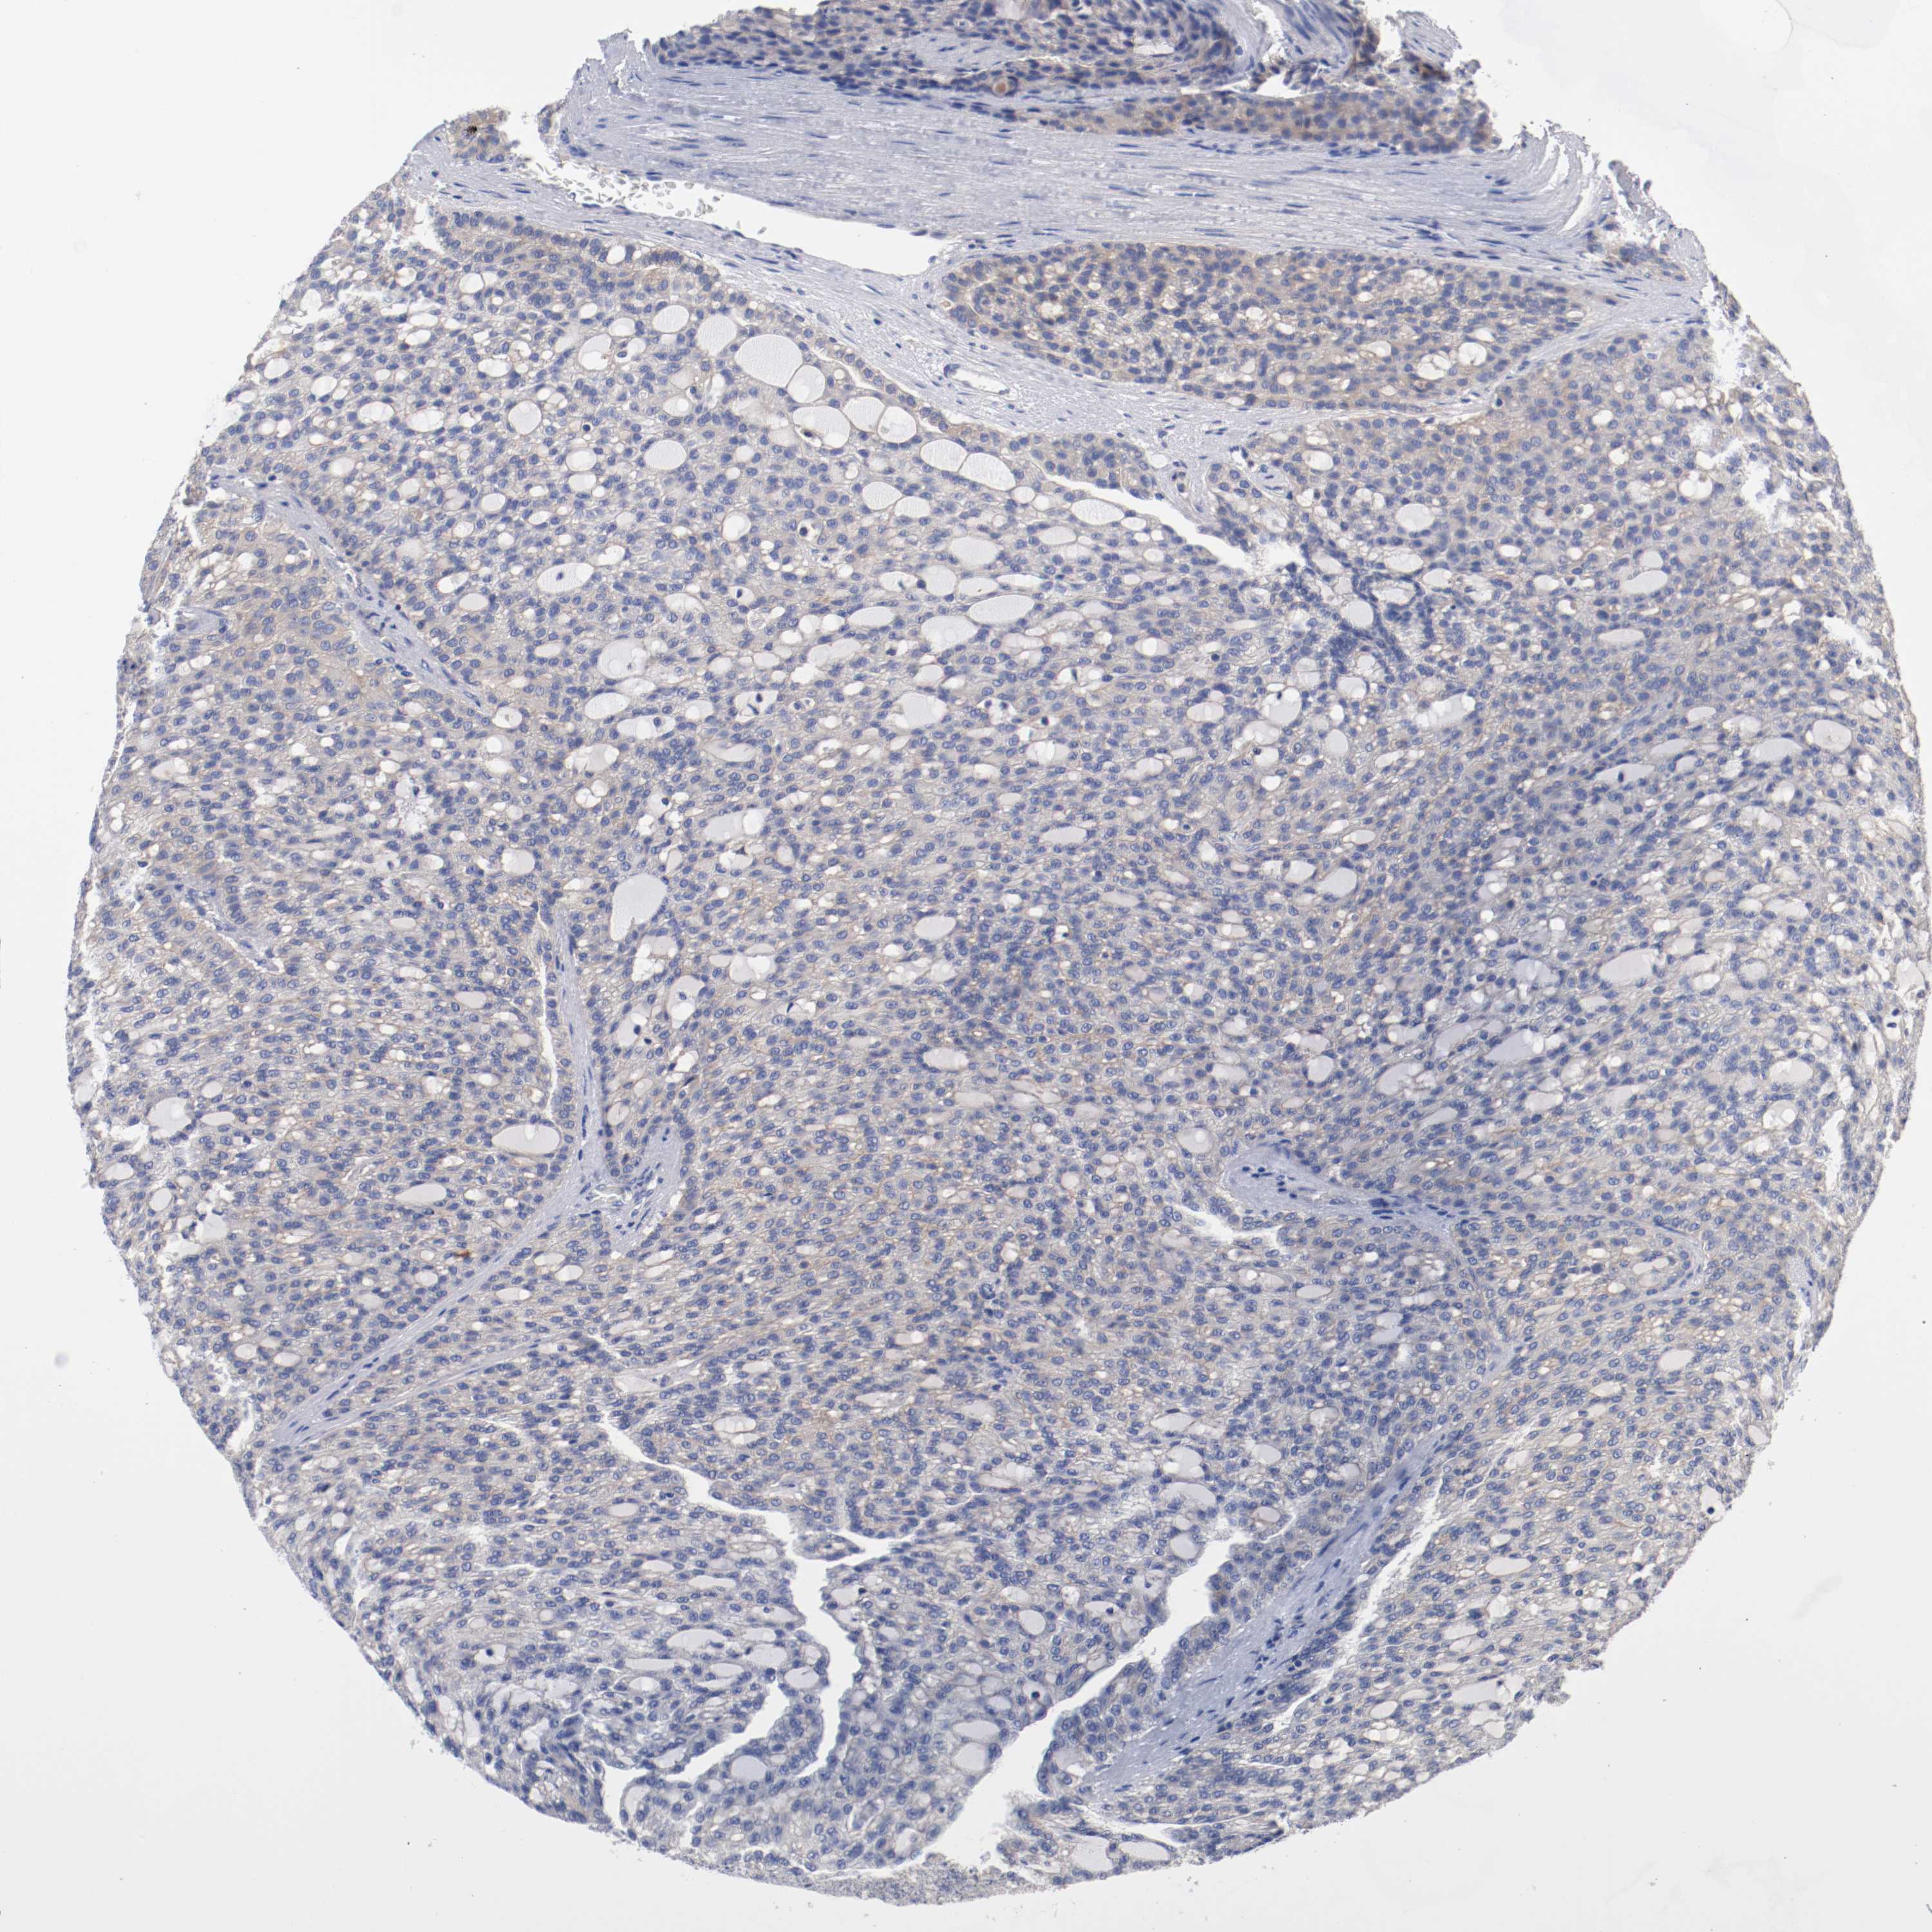

KICH TCGA KIRC TCGA KIRC VALIDATION KIRP TCGA PROTEIN RCC CPTAC PROTEIN EXPRESSION

ANTIBODIES

AND

VALIDATION